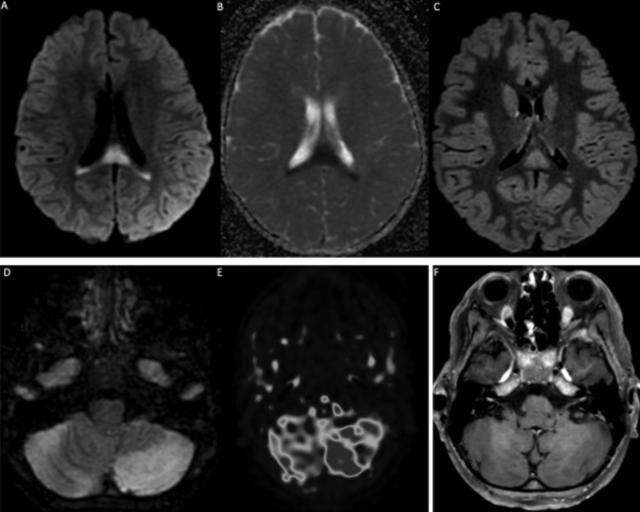

研究者对2名长新冠患者进行了动脉血样动态60分钟[18F]DPA-714PET扫描。为了评估示踪剂代谢,研究者将两名长新冠患者血液中的[18F]DPA-714代谢物与所有其他可用受试者的血液中的代谢物进行了比较。他们评估了全血中的活性浓度,校正了来自动脉血样本的注射活性和示踪母体分数。

研究发现,长新冠患者1在所有脑区的[18F]DPA-714结合严重升高。其2T4k_VB模型获得的全脑灰质定量BPND(=k3/k4)相对于健康对照受试者平均增加了121%。长新冠患者2的[18F]DPA-714结合也升高了,从2T4k_VB模型获得的全脑灰质BPND(=k3/k4)相对于健康对照受试者平均增加79%。